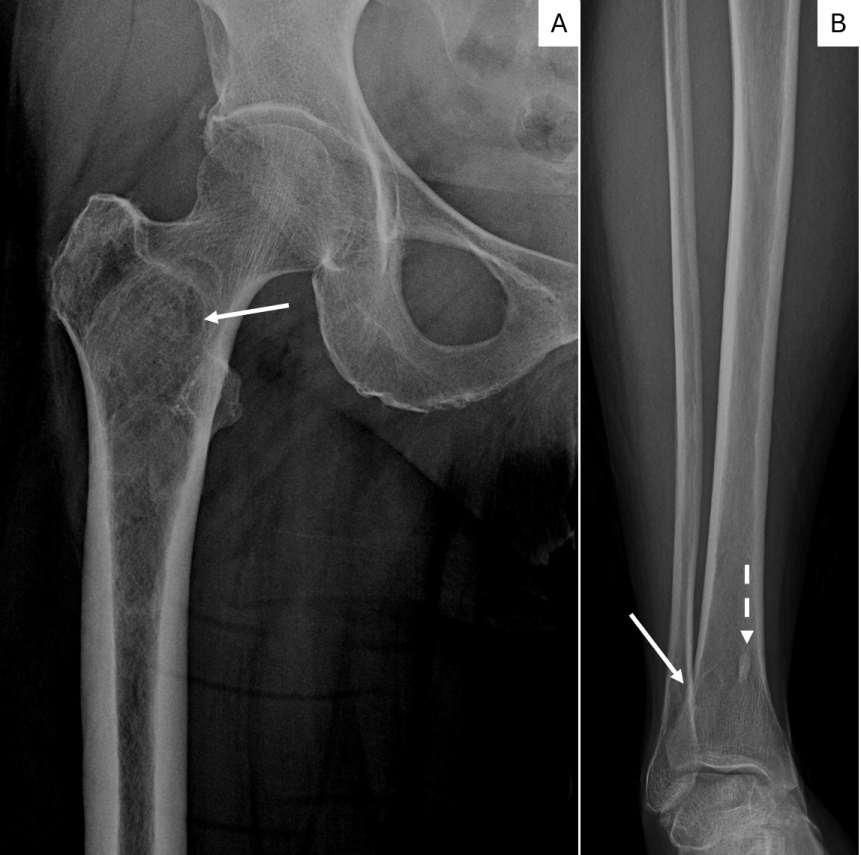

Figure 4: Figure 4a. X-ray of the right femur shows a intramedullary intertrochanteric/subtrochanteric lesion in the right femur with minimal expansion of proximal diaphysis without aggressive cortical involvement. Sclerotic rim, minimal expansion and ground glass appearance suggest Fibrous Dysplasia. (arrow).

4b. X-ray of the tibia shows a metaphyseal osteolytic lesion with smooth to sclerotic rim of FD in right distal tibia superimposed with normal trabeculae (white arrow). A bone island is also present in the medial tibia (dashed arrow). View Figure 4

A 55-year-old woman presented to our tertiary care facility referred from an outside institution after a 3 cm mass in her left breast was identified (Figure 1). The mass was biopsied, and she was subsequently diagnosed with a high grade invasive ductal carcinoma (IDC) (Figure 2). The cancer was negative for estrogen receptor, progesterone receptor and Her2. Additionally, the proliferative rate as assessed by Ki-67 was 85 percent. An axillary lymph node was suspicious by imaging, but not biopsied. A nuclear medicine bone scan with a Tc-99 m radiotracer was used to stage her cancer (Figure 3). The imaging showed increased radiotracer uptake in the right proximal femur and right distal tibia suggestive of metastases and therefore, the patient was considered to have stage IV metastatic breast carcinoma. However, radiographs of the right femur and tibia showed stable lesions without aggressive cortical involvement and a ground glass appearance suggestive of fibrous dysplasia (Figure 4A and 4B). A subsequent biopsy of the proximal femur lesion showed atypical fibrous tissue with S-shaped woven bone trabeculae that tested negative for MDM2 amplification, essentially ruling out low grade osteosarcoma which can sometimes histologically mimic FD [11] and confirming the imaging impression of fibrous dysplasia (Figure 5). Additional genetic testing showed that the fibrous dysplasia was caused by a somatic mutation on codon 201 of the GNAS gene, substituting cytosine in CGT for thymine (TGT). As the fibrous dysplasia was found incidentally as part of the patient’s metastatic work up and was generally asymptomatic, it was clinically followed. Her triple negative breast cancer responded to preoperative chemotherapy, and a subsequent left breast segmental mastectomy showed only treatment related changes and no residual disease. The sentinel lymph nodes were negative for metastatic carcinoma. The breast specimen was evaluated by molecular sequence analysis which revealed no mutation in exon 8 or 9 of the GNAS gene. The patient is currently well with stable polyostotic fibrous dysplasia and without residual carcinoma.